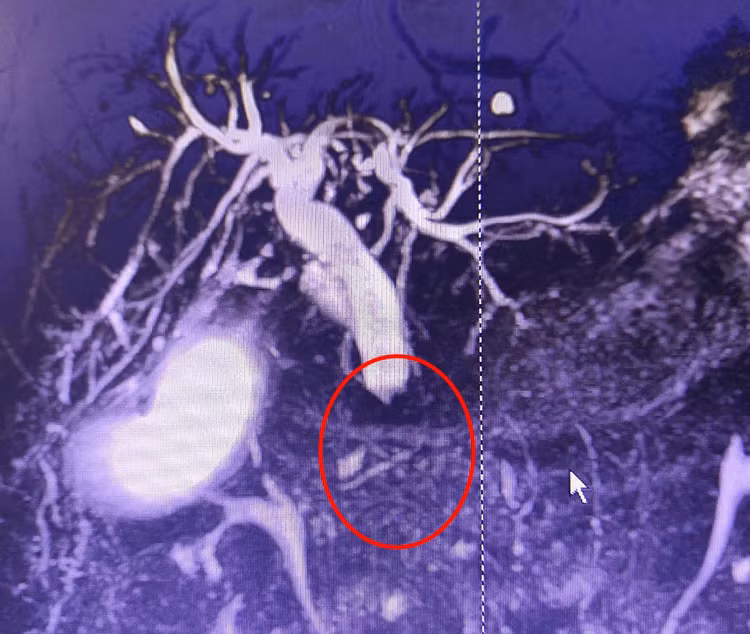

![]() |

| Hình ảnh phần thấp ống mật chủ bị chít hẹp hoàn toàn do u - Ảnh BVCC |